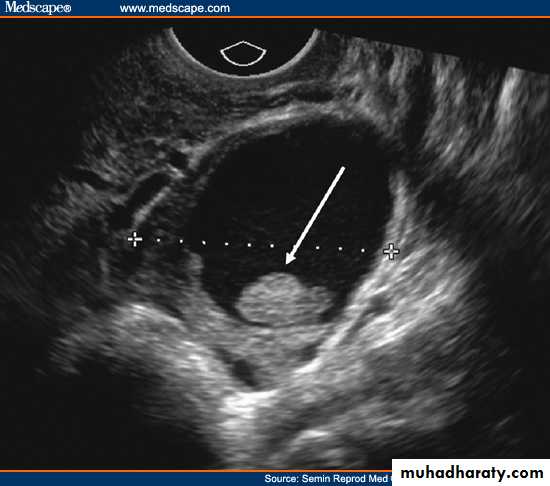

Hemorrhagic cyst of ovary with ruptured ectopic pregnancy:

This female patient has a left ovarian hemorrhagic cyst (see ultrasound image above-left). In addition, there is a large collection of free fluid with particulate matter in the pelvis. The right fallopian tube is thickened with a ring shaped mass. This suggests that there is significant hemorrhage into the pelvis due to a ruptured ectopic pregnancy (right tubal ectopic gestation). The left ovarian hemorrhagic cyst appears intact, ruling out ruptured hemorrhagic cyst.